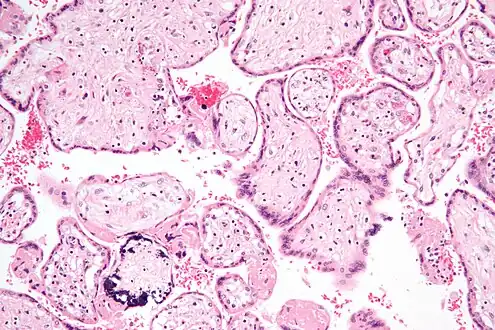

Micrograph of CMV placentitis